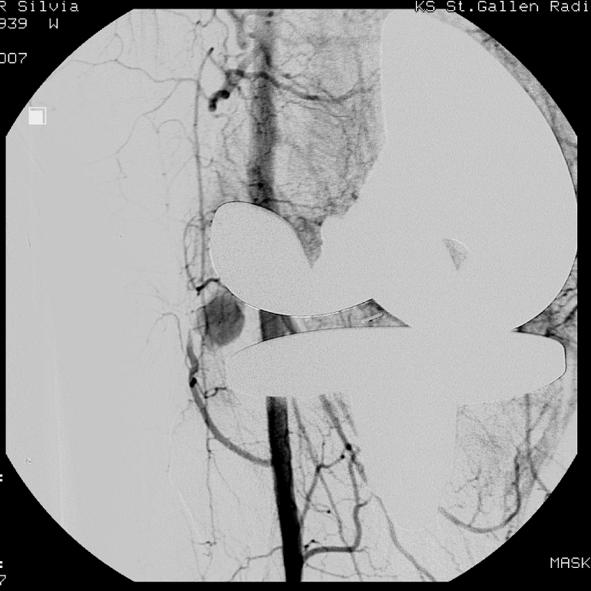

This report describes a case of spontaneous recurrent hemarthrosis of the knee that presented 4 weeks after total knee arthroplasty. Femoral arteriography showed a false aneurysm of a branch of the inferior lateral geniculate artery. Therapeutic embolization of the arterial branch was performed using three platinum coils with good clinical result and good knee joint function. Hemarthrosis has not recurred since embolization.

本报告描述了一例全膝关节置换术后 4 周出现膝关节自发性反复关节积血的病例。股动脉造影显示,膝下外侧膝状动脉分支假性动脉瘤。使用三根铂金线圈进行动脉分支的栓塞治疗,取得了良好的临床效果和膝关节功能。栓塞后关节积血未再复发。